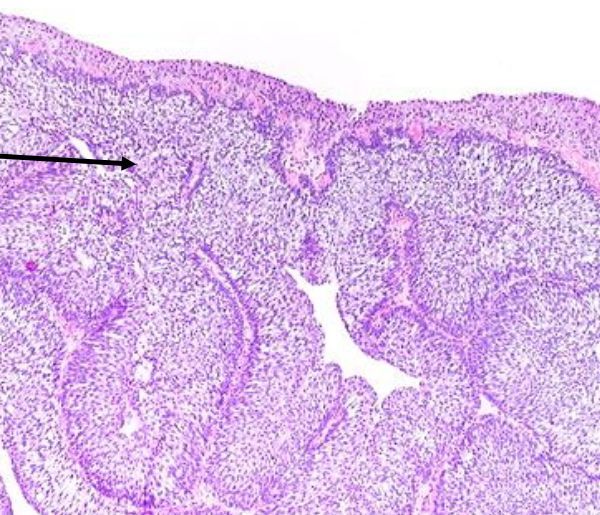

Von Brunn nests

Invaginations of the surface urothelium into underlying lamina propria. Normal urothelium thickness & cytology. Round shape (not infiltrative), uniform size

You should be thinking urothelial carcinoma if instead there are many small nests of irregular size that are stacked on-top of one another.